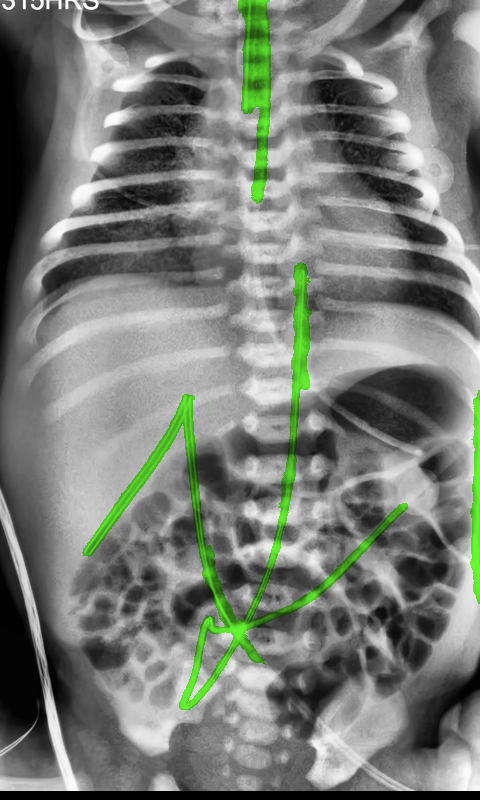

Automated catheter detection is a challenging task. Although most catheters have a radiopaque strip to facilitate detection, the strip may become less apparent depending on the projection angle. Catheters maybe confused by other similar linear structures like ECG leads and anatomy including ribs. Additionally, portions of catheters can be occluded by anatomical structures given that radiographs are a 2D projection of a 3D structure. For example, when a NGT is placed within the oesophagus, the catheter itself becomes less apparent due to the high density of the adjacent vertebrae. Finally, the number and type of catheters that could possibly appear in pediatric X-rays are unknown a priori. The catheters may be intertwined with each other thus making simple line tracing methods fail. Figure 1 gives three sample pediatric X-ray images with some common catheters highlighted in different colors.

To alleviate this annotation problem in catheter detection, we proposed to use X-ray images with simulated catheters by exploiting the fact that catheters are essentially tubular objects with various cross sectional profiles. To be more specific, a synthetic 2D projection of a catheter is generated by first simulating a horizontal catheter profile and then using it as a brush tip to draw along a B-spline path. This generated catheter is then composited with an X-ray image serving as the training data. Another contribution of this work is a segmentation network that can inherently take into account multi-scale information. This network adopts a UNet-style form and contains a recurrent module that can process inputs with increasing scales111Our code is available at https://github.com/xinario/catheter_detection.git.. We have empirically shown that by iterating through the scale space of the input image, higher recall is achieved as compared to using a single scale. Details about the methods are discussed in Section 3. Three sample detection results are shown in Figure 1.

The test dataset is collected locally and only contains frontal chest-abdominal X-rays from patients < 4 weeks old. This is the most common radiograph obtained to confirm placement of catheters such as UACs and UVCs in neonates. Currently, the test set has 35 fully labeled images with different catheter types with sample images previously shown in Figure 1. All the annotated catheters (lines excluding ECG leads) are treated as the same class in the detection.